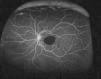

Clinical presentation and acuities were unchanged at the consultation. The retinal specialist diagnosed the patient with multilevel retinal hemorrhage likely secondary to RAM. Fluorescein angiography (FA) was requested to evaluate for leakage from the presumed RAM. FA in the right eye was unremarkable except for a focal area of hyperfluorescence superior-nasal to the macular region consistent with the isolated microaneurysm seen on DFE. The left eye showed complete blockage of fluorescein in the macular region (Fig. 2). There was no leakage visible in the presumed location of the macroaneurysm, making a diagnosis of RAM inconclusive. After discussion of treatment options with the patient, including observation versus risks and benefits of surgery, a pars plana vitrectomy (PPV) procedure was elected to remove the pre-retinal blood for improved retinal visibility and to determine a definitive diagnosis.